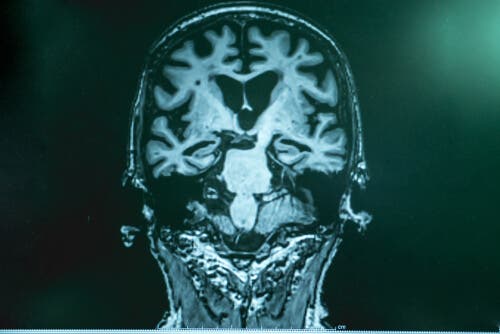

Dr. Lopera forklarer at Alzheimers sykdom er en slags ansamling av “søppel” i hjernen. Det består av et protein som heter amyloid. Fragmenter av det holder seg sammen og danner et slags “lim” som fester seg til nevronene og forårsaker en rekke funksjonsfeil i hjernen. Den andre delen av “søpla” er tau, som vikler seg rundt nevronet, “låser” det og dreper det. Tau er mer skadelig.

Etter nøye studier i Boston fant eksperter at pasientens hjerne var fylt med amyloid, enda mer enn i andre tilfeller. Hun hadde imidlertid veldig lite tau. Forskningen tillot dem å verifisere at en annen mutasjon hemmet produksjonen av tau hos denne pasienten, og det var dette som forsinket utviklingen av sykdommen.